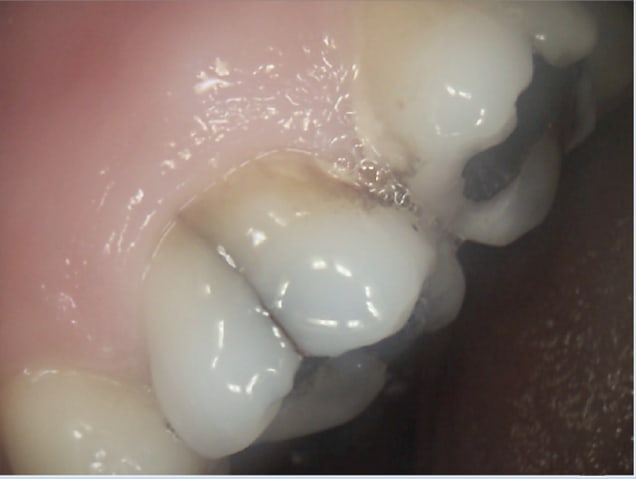

Moi capteur rvg, ca me suffit largement. La manipulation des plaques est éliminatoire pour moi.

Pas suffisamment fin pour détecter cette fêlure sur cette 26 qui sera à extraire ( infection, pas de vitalité) mais une radio argentique n'aurait pas fait mieux. -)